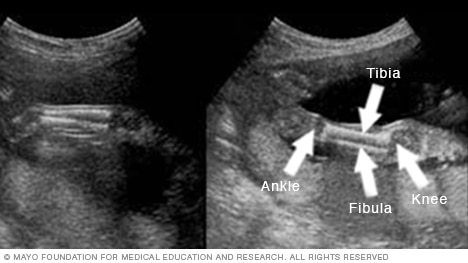

Las piernas

En la imagen se muestra el fémur, que es el hueso de la pierna que va de la cadera a la rodilla. Es el hueso más largo y fuerte del cuerpo.

Más abajo hay imágenes de la parte inferior de las piernas. La rodilla está del lado derecho en las imágenes, y el tobillo, a la izquierda. También se puede ver la tibia y el peroné, el pequeño hueso de la pierna situado en la parte exterior del tobillo.